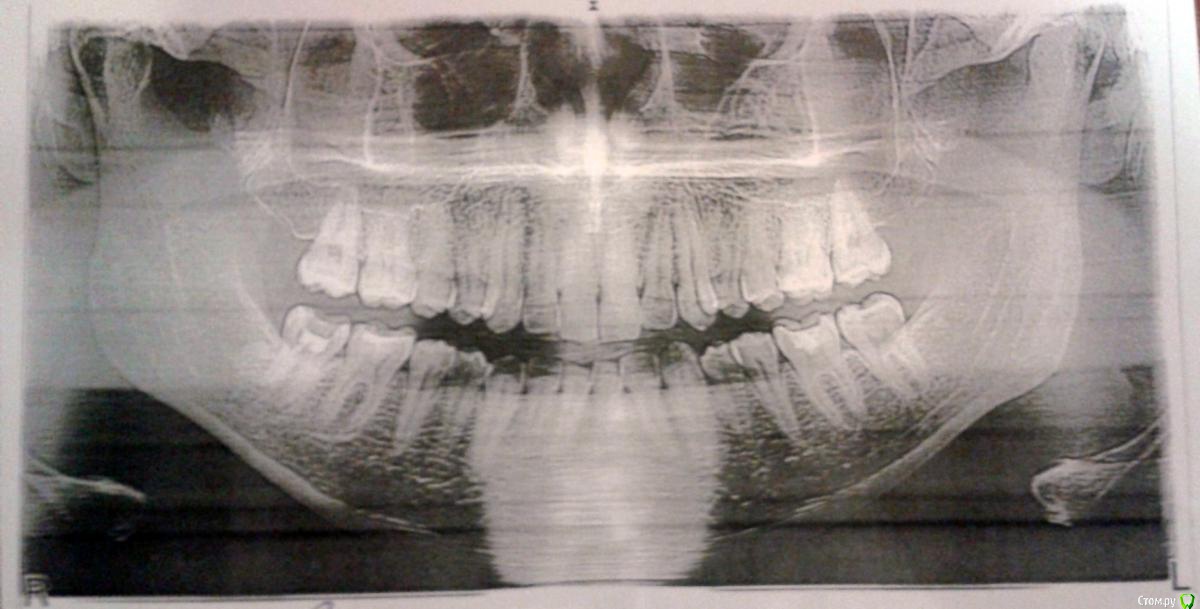

6467t655576 Опубликовано 25 января, 2019 Поделиться Опубликовано 25 января, 2019 (изменено) Здравствуйте.Уже несколько лет беспокоят чередующиеся онемение, боль, непонятные пульсации справа, в районе нижней семерки, хотя дискомфорт нередко охватывает и верхние, и до пятёрок. Удалил все кривые восьмерки - не то. Чуть больше года назад лечил 47, но как-то лучше не стало. Врачи отправляли к неврологу, недавно увидели небольшое воспаление и кололи линкомицин - положительный результат держался меньше недели. На последней оптг узрели кисту, требующую немедленного лечения.Прошу вашего мнения, что видно на снимках, и как с этим бороться (резать десну, "перепроходить" каналы, или правда неврология)?Снимок 47 совсем свежий (дважды, не знаю, какое фото лучше), оптг снимок и фото с монитора в рентгенкабинете около месяца, старая оптг сделана летом. Изменено 25 января, 2019 пользователем 6467t655576 Ссылка на комментарий

kramer Опубликовано 25 января, 2019 Поделиться Опубликовано 25 января, 2019 Мне кажется, здесь картина неврита тройничного нерва и накладывающиеся на него симптомы периодонтита ("киста") зуба 47. Две отдельные проблемы, решать их надо отдельно. 1 Ссылка на комментарий